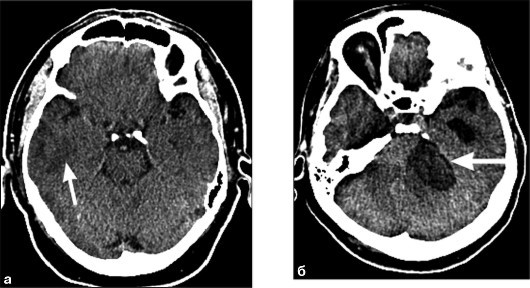

- кровоизлияния;

| Травма головы с подозрением на перелом височной кости | Линейные переломы, вдавленные переломы, гематомы (эпидуральные, субдуральные, внутримозговые), пневмоцефалия, повреждение слуховых косточек | Определение тактики лечения (консервативное/хирургическое), оценка риска осложнений (менингит, потеря слуха, парез лицевого нерва) |